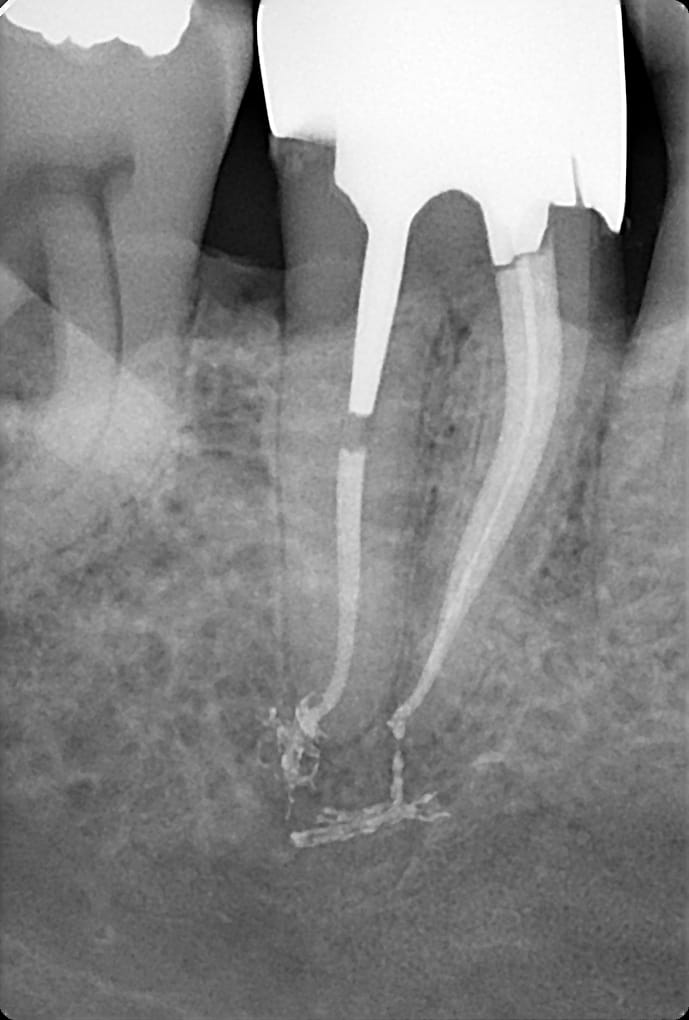

T'as plein d'inlay cores avec reprises de carie aussi je peux t'en poster des caisses.

Iv3t8q7ou8hri4y8gsnyw7gprqbd - Eugenol

C'est quoi le souci c'est la limite composite dent ? Si c'est au sec aucun souci sinon les indications des composites seraient très limitées. Bon là c'est un cas extrême mais tu fais tes RCPE avec des matrices au sec, ton endo et ensuite restauration avec screw post pas de raison que ça se carie. Les inlay cores scellés dans le sang en one shot avec la couronne ça marche moyen aussi. Les composites foulés dans la salive ça marche pas ca marche pas non plus avec une vis.